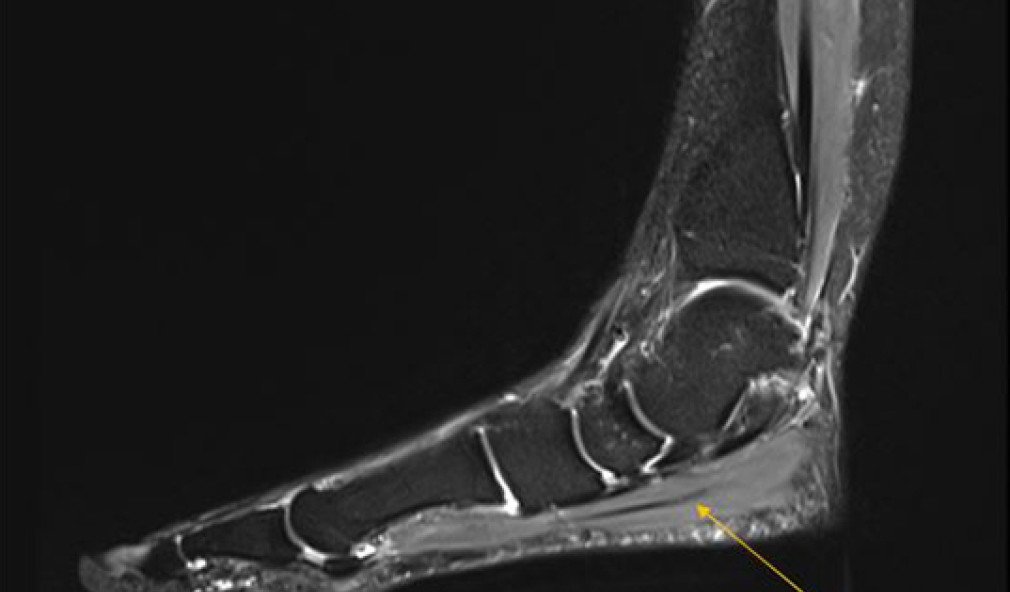

Read more about Fall des Monats: Posttraumatische Instabilität im unteren Sprunggelenk nach Gleitschirmunfall

Fall des Monats: Posttraumatische Instabilität im unteren Sprunggelenk nach Gleitschirmunfall

Eine Patientin erlitt bei einem Gleitschirmunfall mehrere Verletzungen an den Füssen und Sprunggelenken. Erfahren Sie im Fallbeispiel, wie nach der ersten Behandlung und Verheilung die posttraumatische Instabilität im unteren Sprunggelenk diagnostiziert und behandelt wurde.